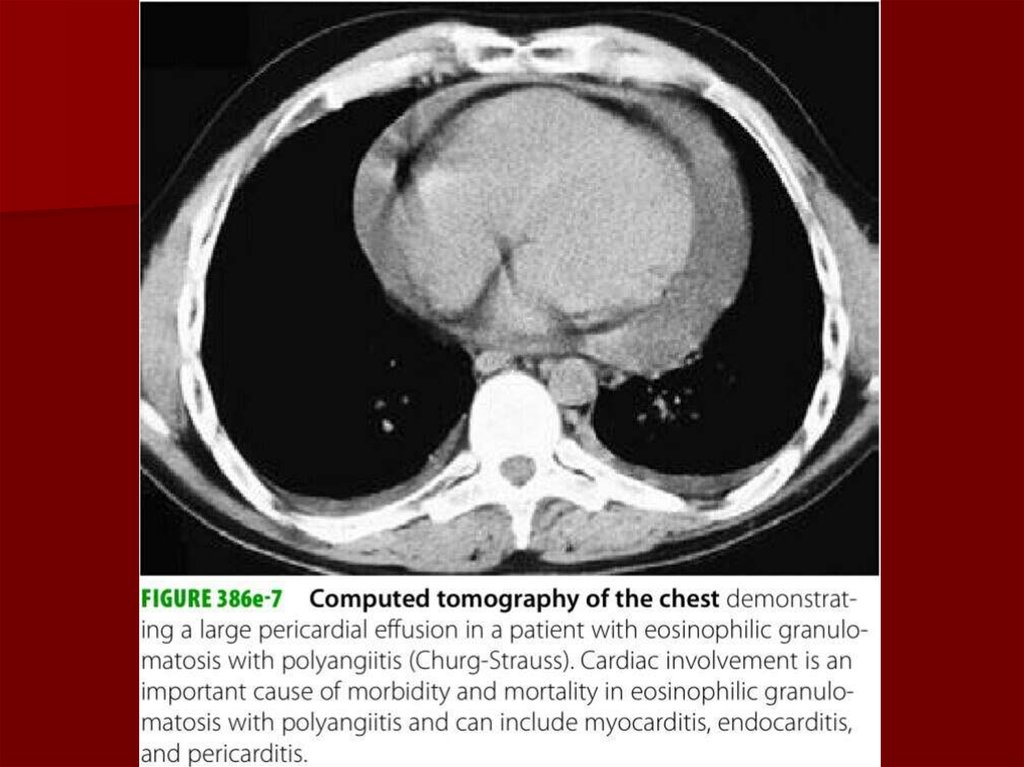

39. Диагностика